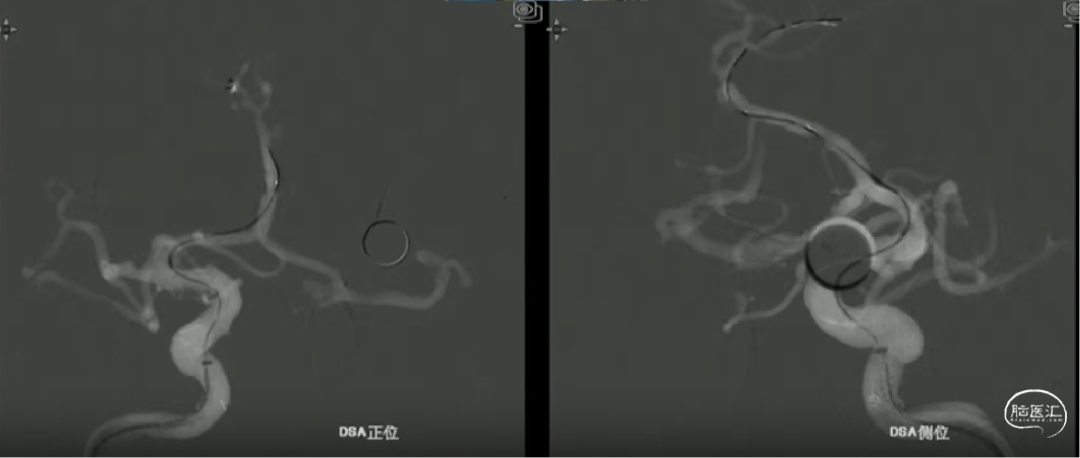

心玮DMC21微导管到位

颅内支撑导管上至C4段,心玮DMC 0.021inch 支架微导管通过颅内支撑导管,经微导丝超选至A4段。

术前测量

远端锚定点:1.5mm

瘤颈远端:1.53mm

瘤颈近段:2.4mm

动脉瘤瘤体直径:4.40mm